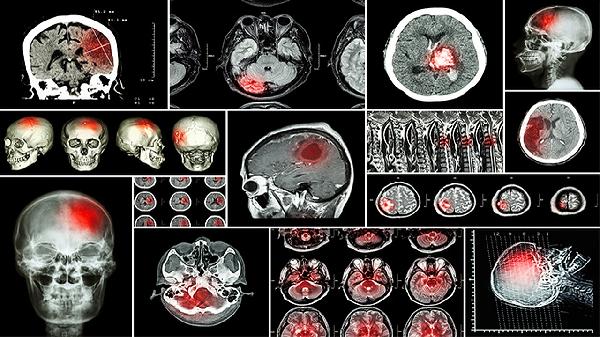

闭合性脑损伤有哪些常用的手术方式

闭合性脑损伤常用的手术方式有去骨瓣减压术、颅内血肿清除术、脑室引流术、颅骨成形术、脑脊液分流术。